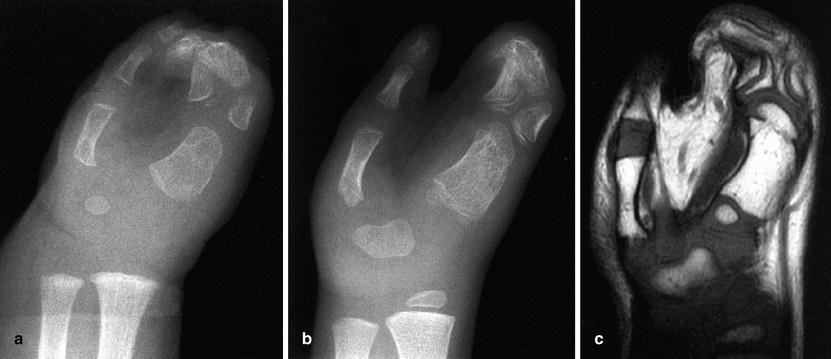

View Delayed Ossification Of Carpal Bones Gallery. To determine if the degree of ossification of the cuboidal bones is associated with. The term carpus is derived from the latin carpus and the greek καρπός (karpós), meaning wrist.

The eight carpal bones run in two rows of four. Ossification of the wrist can be divided into two components: Learn vocabulary, terms and more with flashcards, games and other study tools.

The arrangement of carpal bones in two rows poorly correlates with the wrist's kinesiology* but is universally accepted as the main anatomical classification. Carpal bones, their names, ossification time and how to remember it easily. The most common form of fused carpal bones or carpal coalition is of the scaphoid and lunate. Scaphoid, lunate, triquetrum, and pisiform make up the proximal row running from the radial to ulnar in the normal wrist, adjacent carpal bones demonstrate motion limitations specific to a given intercarpal joint.